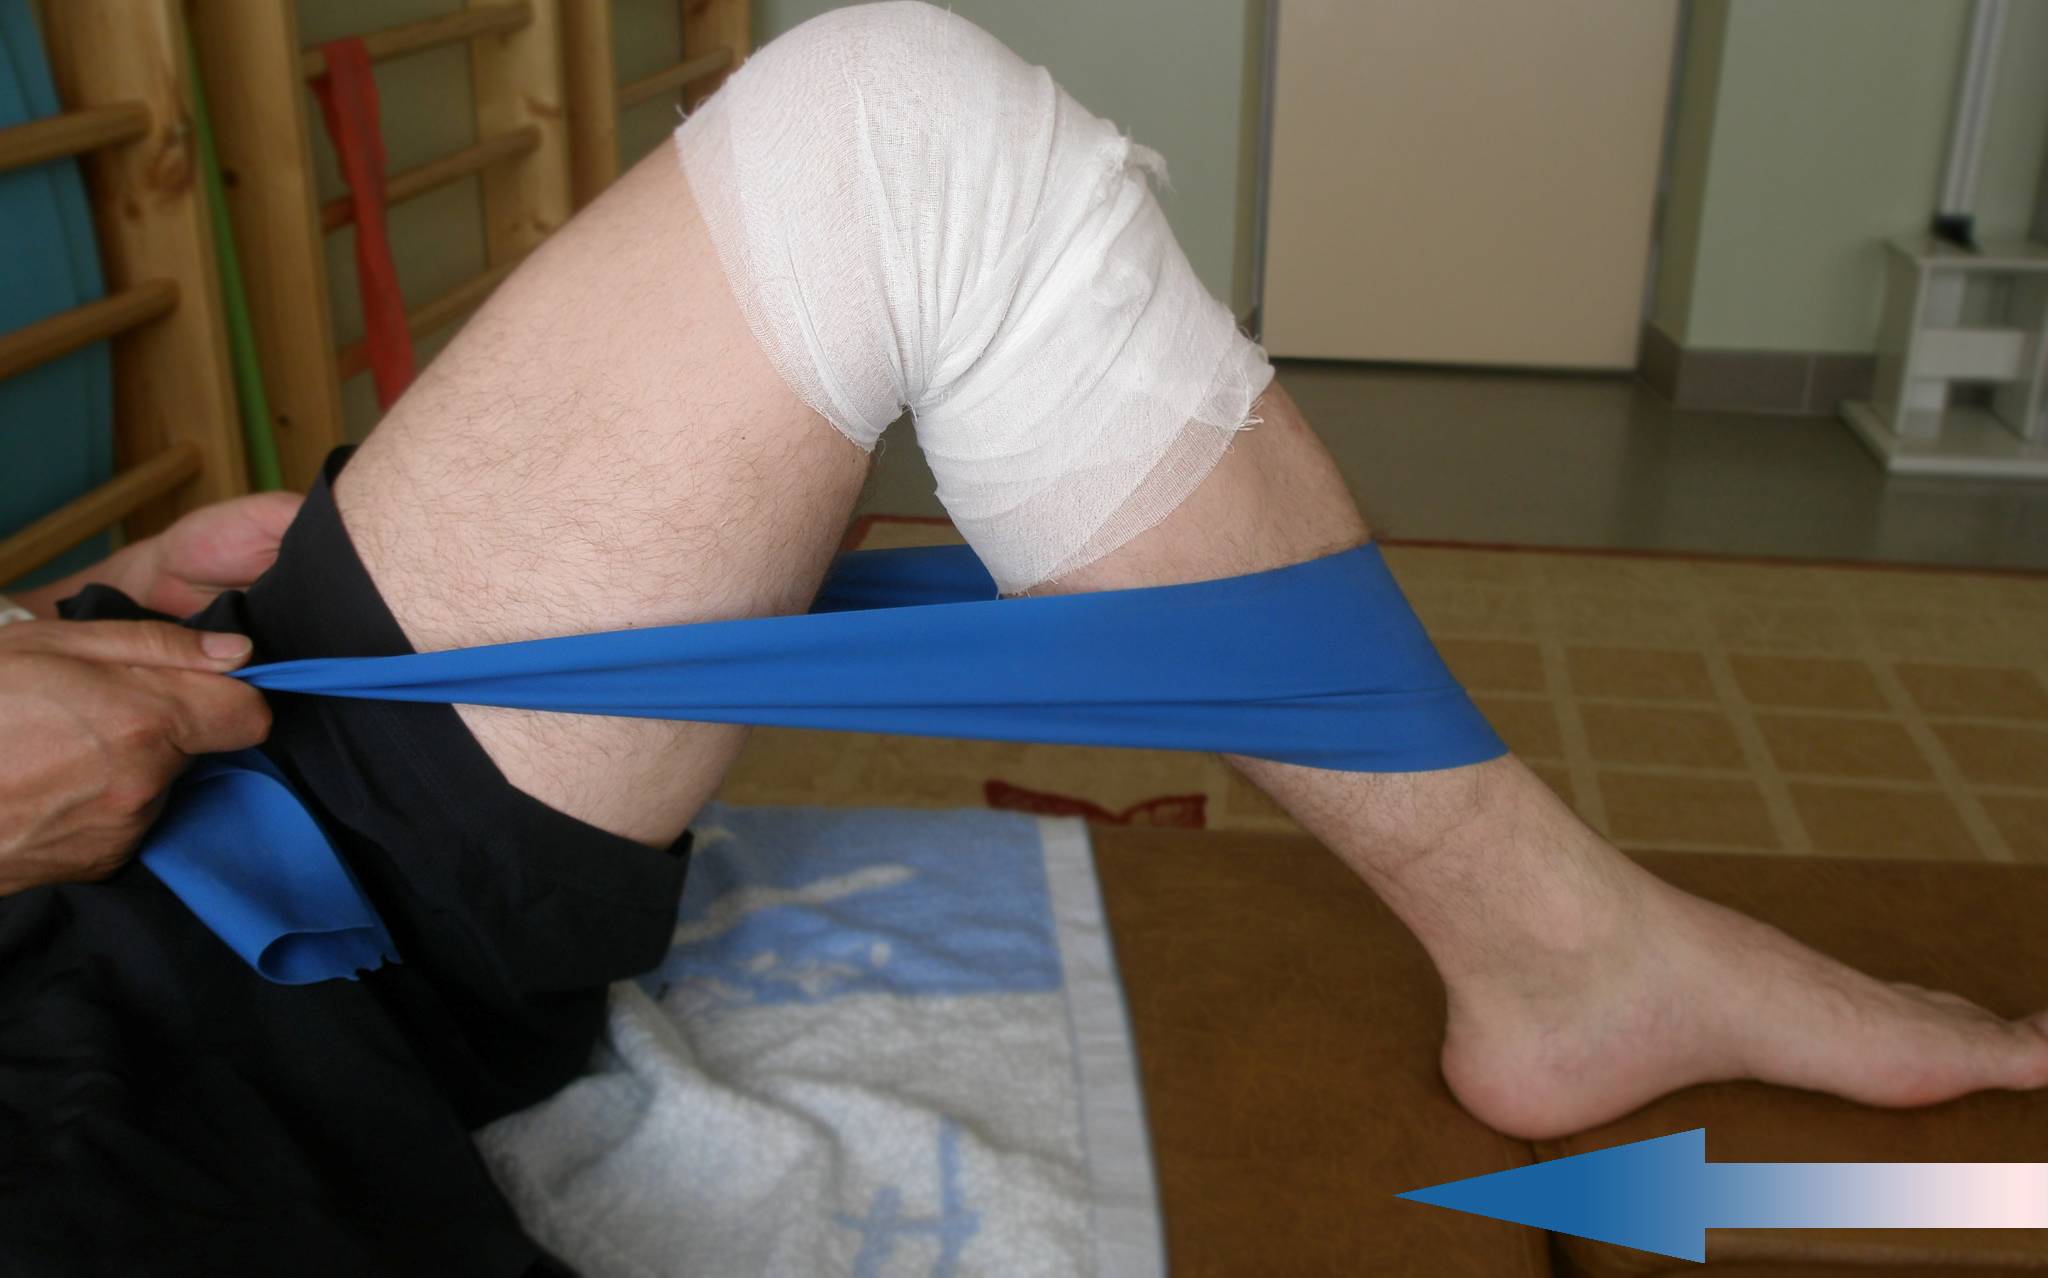

- Упражнения из комплекса ЛФК.

- Кинезиотерапия.

- Применение специальных ортопедических тренажёров.